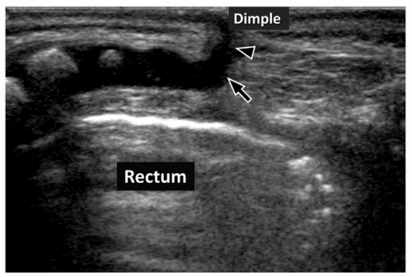

PEDİATRİK SAKRAL ULTRASON

Yeni doğan bebeklerin bazılarında kuyruk sokumu düzeyinde sakral gamze adını verdiğimiz çukurluklar olabilir. Rutin pediatri muayenelerinde saptanan bu bulgunun altta yatan bir sebep olup olmadığının saptanabilmesi açısından mutlaka ultrason ile değerlendirilmesi gerekir.

Sakral gamzesi olan bebeklerde büyük oranda bir problem saptanmamakla birlikte ultrason ile omurilik kanalında açıklıklar ya da omuriliğin daha gergin olması gibi problemler saptanabilir. Bu durumda tedavi gerekebildiği için sakral gamze varlığında ultrason vazgeçilmez bir incelemedir.